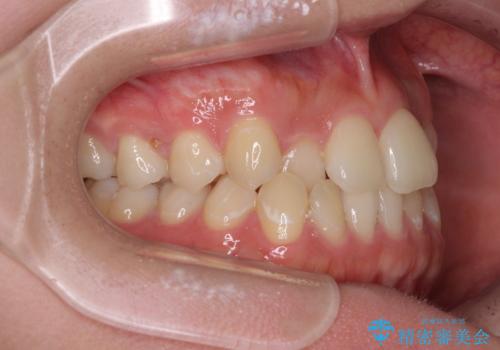

前歯のクロスバイトを短期間で解消 目立たないワイヤー矯正

- 前歯のクロスバイトを治したいとのことで来院された患者様です。

できる限り楽して、短期間で治したいとのことで、ワイヤー装置にて矯正治療を行うこととしました。